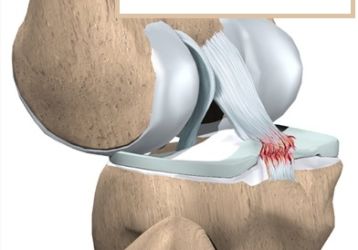

Разрыв задней крестообразной связки: причины, лечение и восстановление

Разрыв задней крестообразной связки: что приводит к травме. Как лечить консервативно и хирургически. Перспективы восстановления подвижности.